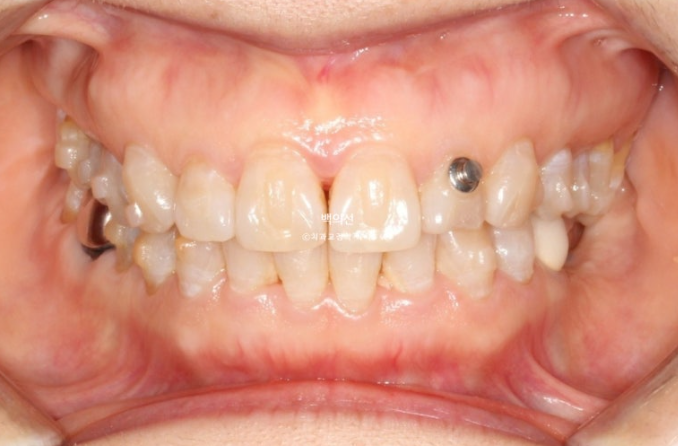

24년 10월부터 25년 2월까지 4개월간 인비절라인 라이트가 허용하는 14개 장치를 모두 낀 후 모습입니다.

25.02

중심선은 정확히 맞고 과개교합은 개선이 되었습니다.

사진상 금속부분은 고무줄 거는 고리이고 치료 도중 해당치아의 이동이 원활하지 않아서 고무줄의 힘을 더하기 위한 부착물입니다.

내려와 있던 제 1대구치가 원래위치로 많이 올라갔습니다.

이제 임플란트 심을 공간이 확보되었습니다.

입천장에 교정용 나사인 미니스크류를 1개 심고 정출된 제1구치 함입을 도모합니다.

아래 앞니 배열은 많이 좋아졌으나 아직 배열이 완벽하진 않습니다.